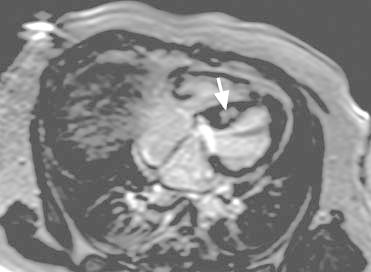

Cardiac magnetic resonance images confirmed noncontiguous hypertrophy involving the basal septal, basal anterior, and apical walls of the left ventricle, as well as the inferior and free walls of the right ventricle (RV). A prominent muscle band in the RVOT contributed to dynamic obstruction across the RVOT (Figs. 4 and 5). Patchy hyperenhancement in the septum, visible in delayed-enhancement sequences after gadolinium administration, was consistent with myocardial fibrosis (Fig. 6). The subendocardium was not involved, suggesting a cause other than coronary disease.

Fig. 5 Cardiac magnetic resonance image shows a hypertrophied muscle band in the right ventricular outflow tract contributing to dynamic obstruction indicated by flow acceleration (arrow).